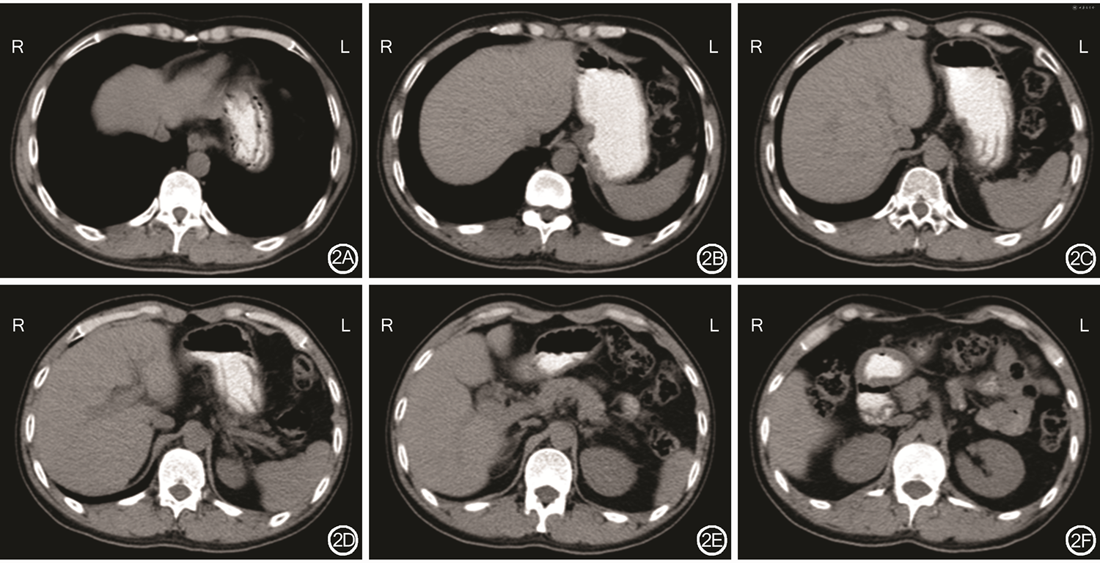

2000年3月24日患者在我院行原位肝移植手术。供者为青年男性,24岁,脑外伤史,既往体健,淋巴细胞实验为2%,符合供者要求。患者病肝病理学检查:符合混合性肝硬化变性,肝组织被粗细不等的纤维组织分割成大小不等的假小叶结节,纤维分割带中含有较多萎缩的肝腺泡和增生的小胆管,以及中等量淋巴细胞、单核细胞浸润,肝细胞普遍浊肿,散见少量嗜酸性病变或点状坏死,肝窦内枯否氏细胞增生(图1)。患者术后恢复顺利,记忆力逐渐恢复正常,对答切题,言语清晰。患者术后随访23年余,可正常生活和工作。术后多次复查腹部CT(图2)及肝脏彩色多普勒超声示移植肝脏形态正常。